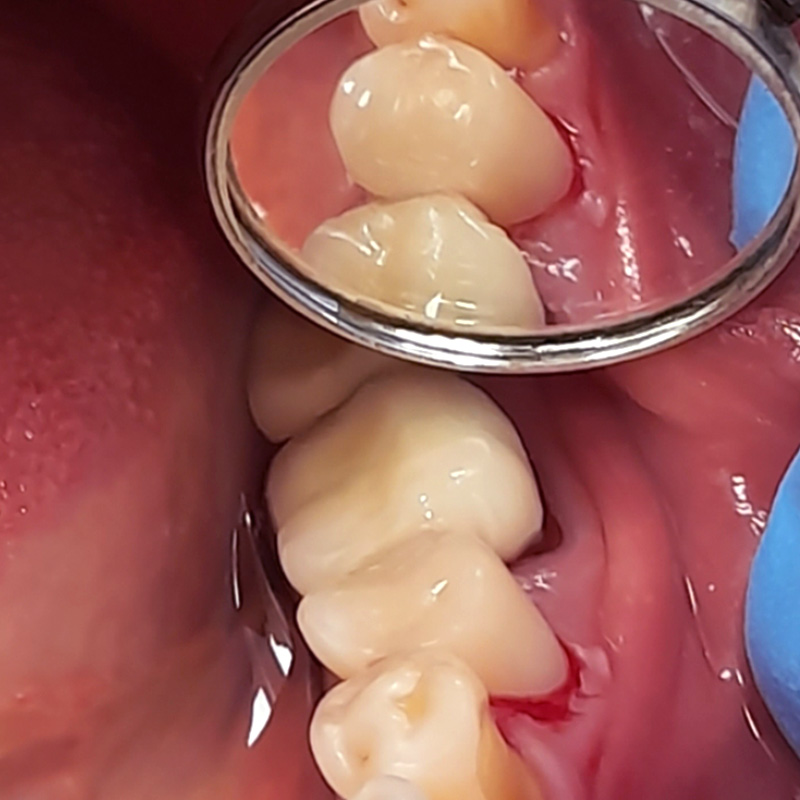

В нашу клинику обратилась пациентка с целью восстановления эстетики зубов на верхней челюсти.

После осмотра и тщательной диагностики врач-ортопед Мельников Алексей Владимирович предложил протезирование коронками из цельной керамики.

Керамические коронки идеальны для высокоэстетичных реставраций в зоне улыбки. Керамика не выделяется в полости рта и обладает естественной светопрозрачностью.

В ходе лечения были проведены следующие работы:

- профессиональная гигиена полости рта;

- препарирование эмали зубов;

- снятие слепков;

- изготовление и установка цельнокерамических коронок на 15-17 зубы.